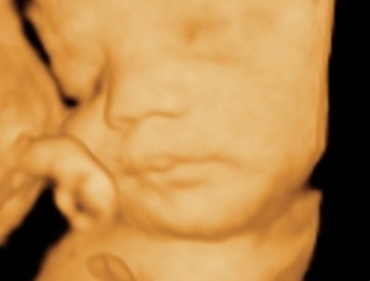

Principala evolutia a copilului fata de saptamana trecute este acumularea rapida de grasime.